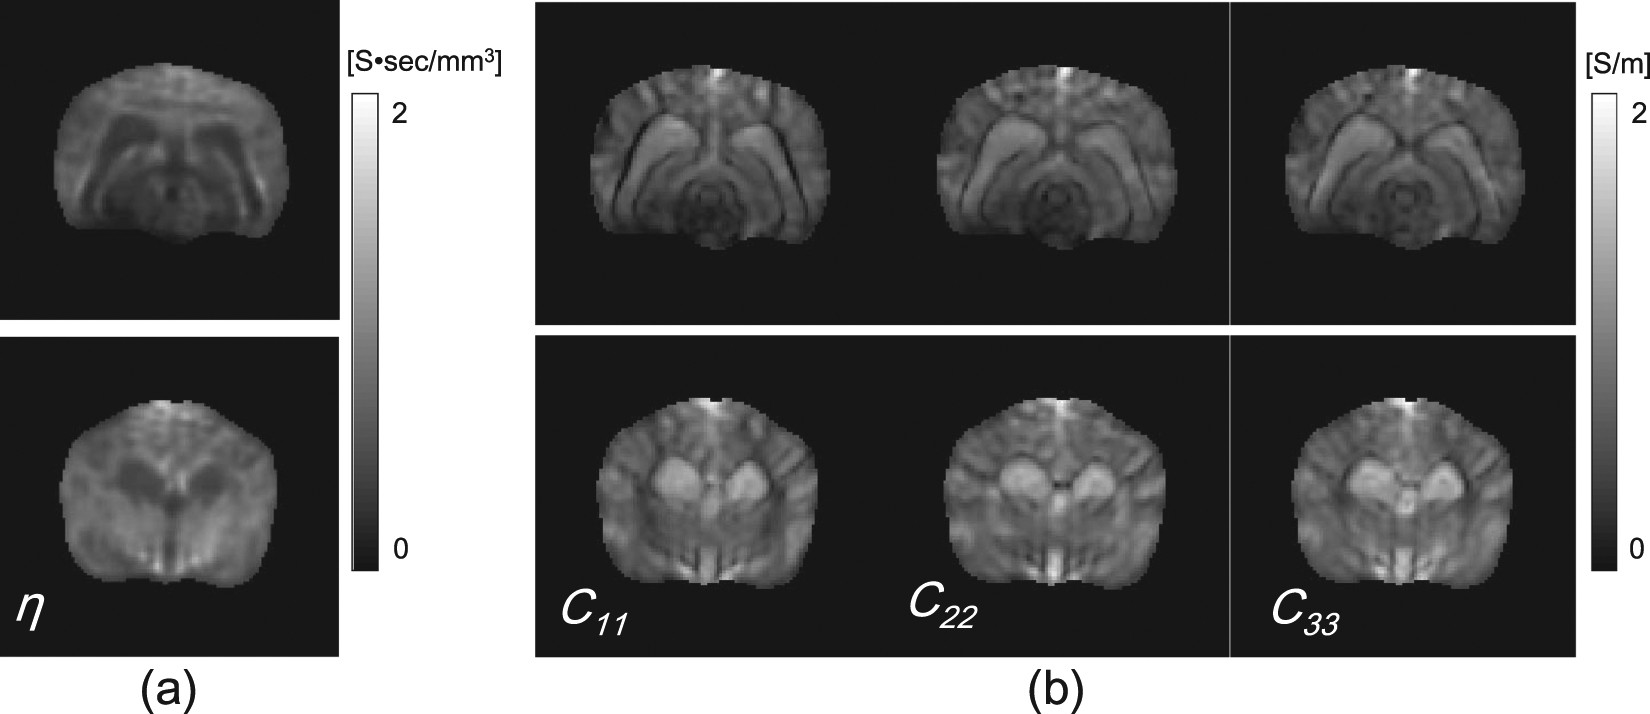

Figure 8

(a) and (b) Recovered EEC and diagonal components of the reconstructed conductivity tensors images using λ opt on the first and second imaging slices, respectively.